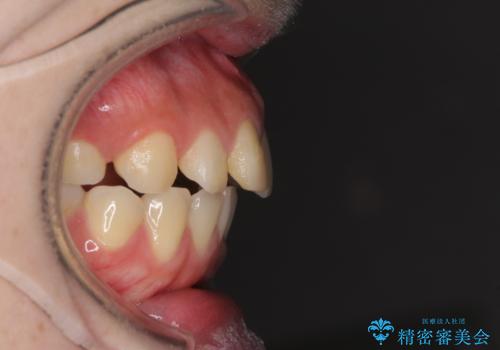

抜歯矯正の後戻り インビザラインによるオープンバイトの再矯正

- 以前矯正治療をされていましたが、後戻りが起きたことを気にして来院された患者様です。

上下前歯のオープンバイトを改善するため、インビザラインにて治療を行うこととしました。